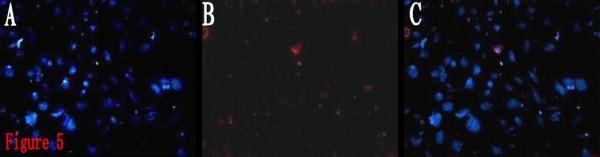

Limiting dilution and clonogenic assay were used to isolate and screen BTSCs from the fresh specimen of human brain glioblastoma. The obtained BTSCs, which were cultured in serum-free medium, were classified into four groups in accordance with the composition of the different treatments. The proliferation of the BTSCs was evaluated by MTT assay. The BTSCs were induced to differentiate in serum-containing medium, and classified into the ATRA group and control group. On the 10th day of induction, the expressions of CD133 and glial fibrillary acidic protein (GFAP) in the differentiated BTSCs were detected by immunofluorescence. The differentiated BTSCs were cultured in serum-free medium, the percentage and the time required for formation of brain tumor spheres (BTS) were observed.

BTSCs obtained by limiting dilution were all identified as CD133-positive by immunofluorescence. In serum-free medium, the proliferation of BTSCs in the ATRA group was observed significantly faster than that in the control group, but slower than that in the growth factor group and ATRA/growth factor group, and the size of the BTS in the ATRA group was smaller than that in the latter two groups(P < 0.01). In serum-containing medium, the expression percentages of CD133 and GFAP in the differentiated BTSCs were (2.29% +/- 0.27%) and (75.60% +/- 4.03%) respectively in the ATRA group, and (7.05% +/- 0.49%) and (12.51% +/- 0.77%) respectively in the control group. The differentiation rate of BTSCs in the ATRA group was significantly higher than that in the control group (P < 0.05), but there was still CD133 expressed in the ATRA group. The differentiated BTSCs could re-form BTSs in serum-free medium. The percentage of BTS formation in the ATRA group was(4.84% +/- 0.32%), significantly lower than that in the control group (17.71% +/- 0.78%) (P < 0.05), and the time required for BTS formation in the ATRA group was (10.07 +/- 1.03)d, significantly longer than that in the control group (4.08 +/- 0.35)d (P < 0.05).

通过有限稀释获得的 BTSCs 均通过免疫荧光鉴定为 CD133 阳性。在无血清培养基中,ATRA 组 BTSCs 的增殖速度明显快于对照组,但慢于生长因子组和 ATRA/生长因子组,ATRA 组的 BTS 体积小于后两组(P < 0.01)。在含血清培养基中,ATRA 组分化后的 BTSCs 中 CD133 和 GFAP 的表达百分比分别为(2.29% ± 0.27%)和(75.60% ± 4.03%),对照组分别为(7.05% ± 0.49%)和(12.51% ± 0.77%)。ATRA 组 BTSCs 的分化率明显高于对照组(P < 0.05),但 ATRA 组仍有 CD133 表达。分化后的 BTSCs 可在无血清培养基中重新形成 BTS。ATRA 组 BTS 形成的比例为(4.84% ± 0.32%),明显低于对照组的(17.71% ± 0.78%)(P < 0.05),ATRA 组形成 BTS 的时间为(10.07 ± 1.03)d,明显长于对照组的(4.08 ± 0.35)d(P < 0.05)。